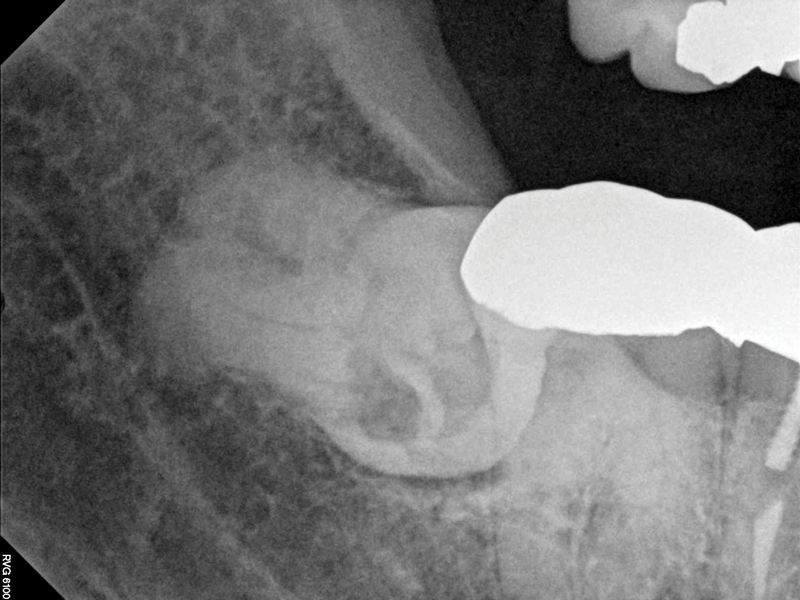

Given the confirmation of a likely odontogenic source of pathology since pain was relieved by the block anesthesia, secondary periapical imaging was taken, which showed intracoronal resorption in the unerupted tooth No. 32 (Figure 4). Because of the visualizable pathology and signs and symptoms consistent with a symptomatic irreversible pulpitis, the patient was referred to an oral and maxillofacial surgeon for extraction of tooth No. 32. The patient reported complete resolution of symptoms following extraction of the affected tooth. Communication from the oral surgeon confirmed the diagnosis of intracoronal resorption on tooth No. 32.

Fig 4. Case 1: Periapical imaging of the maxillary right (Fig 2) and mandibular right (Fig 3) quadrants initially showed no obvious pathology, aside from the horizontally impacted tooth No. 32. Secondary imaging following successful relief of pain after administration of an inferior alveolar nerve block revealed pre-eruptive intracoronal resorption in tooth No. 32 with resultant symptomatic irreversible pulpitis as the likely source of pain (Fig 4).

Figure 4